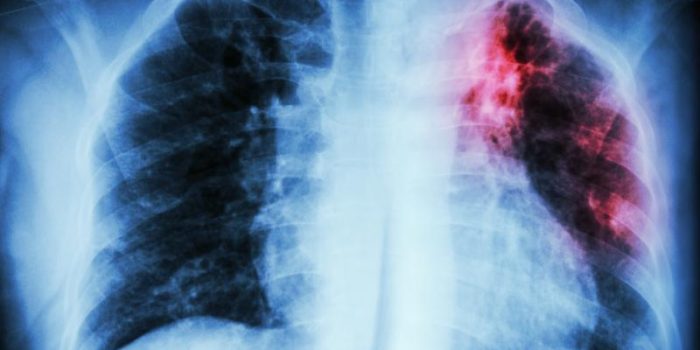

The results of a phase 3 trial conducted in India reveal that two experimental tuberculosis (TB) vaccine candidates did not show efficacy against all forms of TB but were safe and offered limited protection against a more severe form of the disease.

Protection against extrapulmonary TB

Neither vaccine provided protection against all TB, pulmonary TB, and latent TB. But VPM1002 showed a vaccine efficacy (VE) of 50.4% against extrapulmonary TB, which occurs when TB spreads beyond the lungs, and Immuvac had a VE of 33.2% against extrapulmonary TB. VPM1002 and Immuvac showed VE of 64.9% and 66.3%, respectively, against extrapulmonary TB in participants with tuberculin skin-test positivity.

“Extrapulmonary TB, which occurs at sites other than the lungs, occurs in about a third of patients diagnosed as having TB, and the mortality for this form of TB may increase to about 40% in some countries,” the investigators noted.

VPM1002 also demonstrated VE of 64.6% for all forms of TB, 62.1% against pulmonary TB, and 77.6% against extrapulmonary TB in children aged 6 to 14 years, while Immuvac provided protection against extrapulmonary TB only in children aged 6 to 10 years. The confidence intervals for all VE estimates, however, were wide, indicating considerable uncertainty, and the ranges for several dropped below zero, indicating findings that aren’t statistically significant.